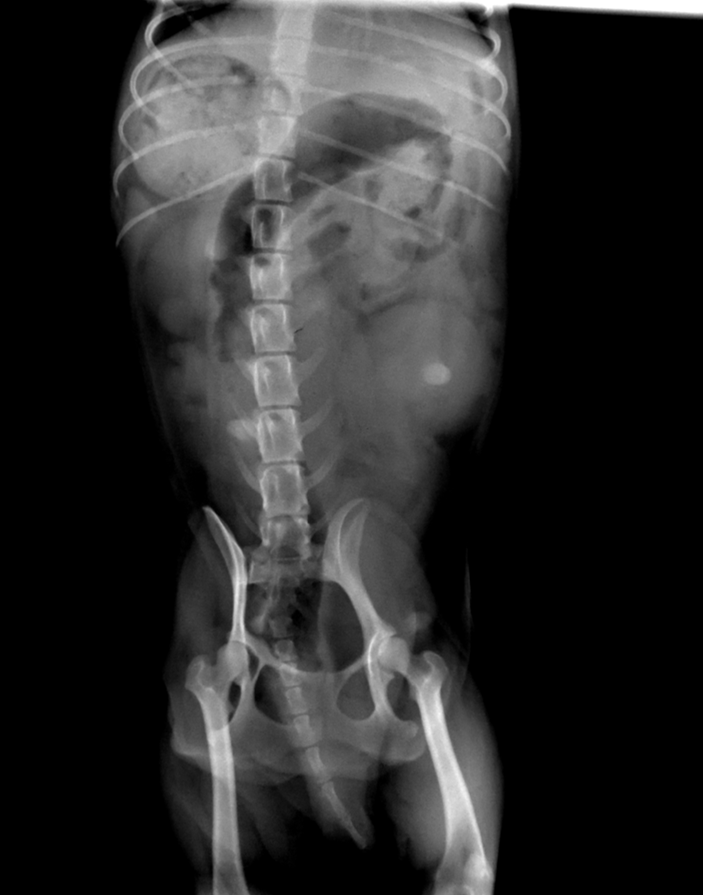

帮我看一下我家狗的片子,狗狗怀孕刚生了宝宝,请尽快告诉我好么!急 点击展开 匿名用户 2015-01-02 22:39 为您推荐: 其他回答 这你要去医院问医生呀!右侧有个大肿块问医生看看是什么,然后对症下药 匿名用户 2015-01-02 23:27 相关问题 狗狗几岁可以生宝宝``怀孕要坏多久``从生下来到死```要打些什么针``请各位懂狗人士告诉我``` 被自家狗咬出血了,狗狗养了12年了,用肥皂水清洗了… 孕六个月,下雨了把狗从笼子里放出来的时候被狗狗挠了腿一道,没破没流血,但还是担心,有什么影响吗